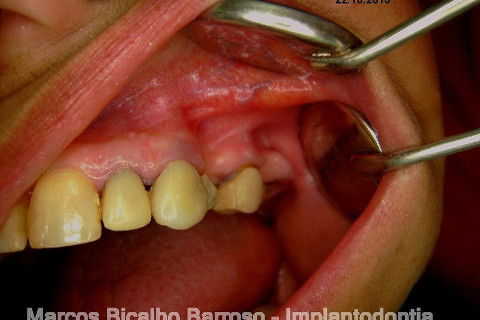

Paciente genêro feminino, 52 anos, procurou meus serviços para resolução de edentulismo parcial, insatisfação com ausência de dentes na região posterior esquerda da maxila, fratura de ponte fixa provisória...

Ao exame clínico já percebemos atrofia no rebordo, uma depressão na vestibular, indicação para enxerto ósseo e dente 27 com indicação para remoção. O plano de tratamento consistiu em levantamento de seio maxilar deste lado para possibilitar instalação de implante na região do 26 (não existe dente antagônico para oclusão com o 27), enxerto ósseo na vestibular do dente 24, aproveitamento do 22,23,25, em situação satisfatória, com indicação de confecção de novas coroas.

A minha intenção era levantamento de seio e enxerto na vestibular do 24 em única sessão, mas a pedido da paciente, resolveremos o caso por etapas, consideramos a prioridade da resolução desta região dos pré molares e fizemos esta cirurgia de hoje, usando osso autógeno coletado da região da tuberosidade e próximo do alvéolo do 27. Usamos também osso bovino liofilizado Bonefill (Bionnovation) granulação média, e tela de titânio Surgitime (Bionnovation). Não foi possível a instalação do implante em conjunto com o enxerto por considerarmos rebordo extremamente atrófico na espessura (menos de 2 mm na crista e menos de 3 mm até acima do terço médio).